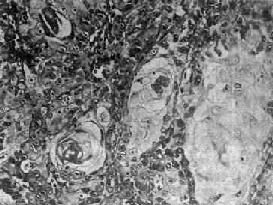

鼻咽泡状核细胞<a href=癌"/>

图9-6 鼻咽泡状核细胞

细胞境界不清,呈合体状,核大圆形,染色质少,呈空泡状,含1~2个肥大的核仁,细胞间有淋巴细胞浸润